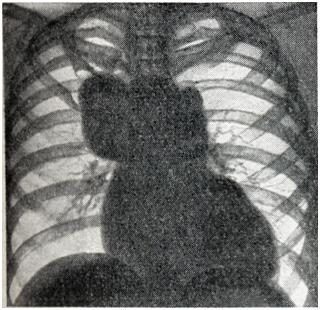

Аневризмы восходящей аорты обычно хорошо определяются в виде выпячиваний на правом контуре сосудистой тени в прямой проекции (рис. 3) и на переднем контуре — в левом косом и боковом положениях. Гораздо реже аневризма располагается на левой стенке восходящей аорты и образует выпячивание слева. Аневризмы дуги аорты (рис. 4) в прямой проекции обычно имеют вид массивной тени над изображением сердца, а в левом переднем косом положении проецируются на область дуги аорты. Аневризмы нисходящей аорты дают добавочные тени по левому контуру сосудистой тени (книзу от первой дуги) в прямой проекции и проецируются на ретрокардиальное пространство и тень позвоночника в косых положениях. Бывают множественные аневризмы аорты. Дифференциальный диагноз аневризмы аорты с опухолями и кистами средостения представляет большие трудности. Признак пульсации имеет лишь ограниченное значение: она может быть передаточной при опухолях и отсутствовать при тромбированной аневризме или сращениях. Рекомендуется применение томографии и пневмомедиастинографии. Кроме обычно встречающихся вторичных признаков — смещения пищевода и трахеи, возможна картина ателектаза легкого вследствие сдавления бронха, высокое положение диафрагмы из-за давления на диафрагмальный нерв, обеднение кровотока в легком ввиду сдавления легочного ствола, атрофия от давления тел позвонков, ребер (рис. 5). Рентгенологическое распознавание аневризмы брюшной аорты по обычным снимкам возможно лишь при наличии обызвествления стенок аорты или типичной деструкции тел позвонков. В предоперационном диагнозе всех аневризм аорты решающее значение имеет аортография.